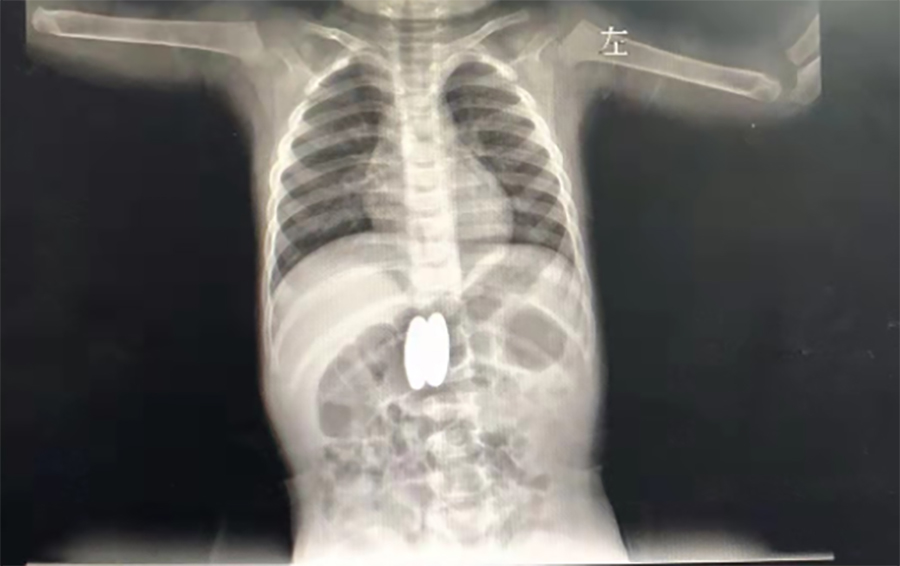

正月初八,2岁的壮壮(化名)感冒加重了,不断咳嗽,家人带他到当地医院就诊。在拍肺CT时,医生发现他的胃、肠里竟然有两个异物,而且两处异物竟吸在一起了。

▲当地医院CT

家长回想起春节前大宝的4个磁力球少了2个,怎么找都没找到,看来是被二宝误吞了。当地医生担心壮壮胃肠穿孔,建议他们马上带壮壮到德州扑克游戏网 就诊。在内镜中心,副主任边鹏经内镜检查,发现壮壮吞下的磁力球直径有2cm,呈椭圆形,分别在胃体后壁、十二指肠球部。考虑到误吞异物时间较长,两球相吸处很可能已经穿孔,内镜中心同外科会诊,迅速研究解决方案。边鹏说,一是手术治疗,但十二指肠周围有胆管、大血管等,周围组织特别敏感,一旦出问题,危险性极大;二是保守治疗,在生命体征平稳的情况下,暂时观察,待胃、肠穿孔形成窦道,就可以不用手术,在内镜下把异物取出来了。经沟通,家长选择保守治疗,择日再来取出异物。